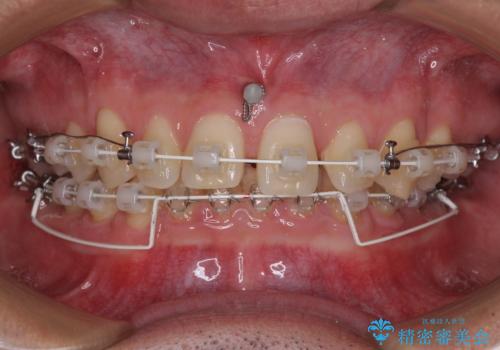

アンカースクリューを用いて下に位置している上顎前歯を持ち上げるとともに、ワイヤー装置によりディープバイトの原因である奥歯の傾斜を改善することで、矯正治療を行っていくこととしました。

顕著なディープバイトのため、頻繁に装置が脱離することがあり、治療期間が想定よりも長くかかることがありますが、当初の予定期間で無事に治療を終えることができました。